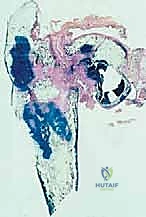

| الخزعة (Biopsy) | أخذ عينة صغيرة من نسيج الورم لفحصها تحت المجهر في المختبر. | الإجراء الوحيد الذي يؤكد نوع الورم (حميد، خبيث، نوع الخلايا)، وبناءً عليه يتم تحديد الحاجة للعلاج الكيماوي قبل الجراحة. |

- ملاحظة هامة حول الخزعة: يُشدد الأستاذ الدكتور هطيف على أن الخزعة يجب أن تُجرى بواسطة الجراح الذي سيقوم بالعملية النهائية، أو تحت إشرافه المباشر. مسار إبرة الخزعة يجب أن يتم التخطيط له بعناية فائقة بحيث يتم استئصاله بالكامل لاحقاً أثناء العملية الجراحية الكبرى، لضمان عدم انتشار الخلايا السرطانية في الأنسجة السليمة.